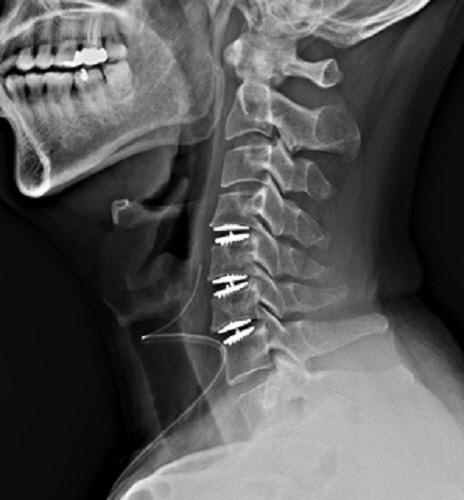

인공디스크는 손상된 디스크를 완전히 제거하고 그 자리에 환자에게 맞춤제작 된 인공디스크를 삽입하는 수술방법으로 실제 디스크처럼 부드럽고 자유롭게 움직일 수 있는 효율적인 수술방법이다.

인공디스크 수술방법은 국소 마취 후 3~4cm가량 절개 후 미세현미경을 통해 병변 부위를 실시간으로 확인하며 손상된 디스크, 뼛조각 등을 제거한 후 인체공학적으로 설계된 최적화 인공디스크를 삽입하는 방식으로 이루어진다.

수술 후에도 본래의 디스크처럼 자유롭게 움직이기 때문에 퇴행성 변화가 가속화될 가능성이 적으며, 최소 절개로 진행되어 안전하고 회복이 빠른 것이 장점이다.